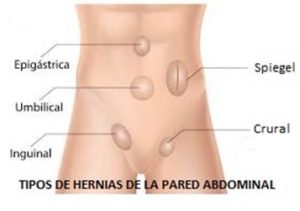

En el caso de la hernia inguinal, el fallo se produce en el llamado anillo inguinal, que por excesiva debilidad y laxitud en la zona, se acaba dilatando en exceso y permite la salida de la hernia.

De manera natural en el varón, por el anillo inguinal salen del abdomen unos conductos que se dirigen al testículo. Los vasos espermáticos y el conducto deferente.

De manera natural en el varón, por el anillo inguinal salen del abdomen unos conductos que se dirigen al testículo. Los vasos espermáticos y el conducto deferente.

En la mujer lo que sale es el ligamento redondo que es un elemento de fijación del útero.

Al dilatarse excesivamente el anillo inguinal profundo, junto a esas estructuras anatómicas descritas, se intruce también la membrana peritoneal también llamado peritoneo, que se convierte en el llamado saco herniario formando lo que llamamos hernia inguinal.

Al dilatarse excesivamente el anillo inguinal profundo, junto a esas estructuras anatómicas descritas, se intruce también la membrana peritoneal también llamado peritoneo, que se convierte en el llamado saco herniario formando lo que llamamos hernia inguinal.